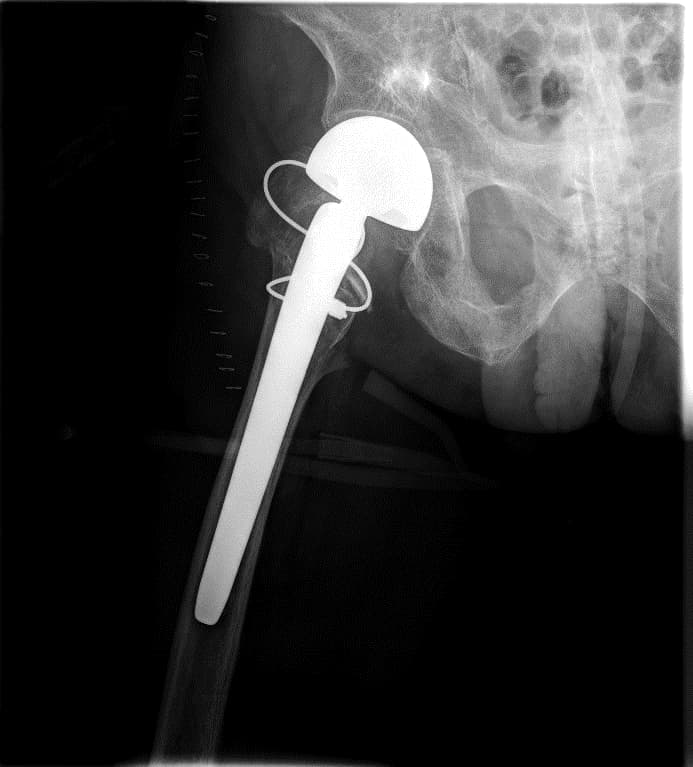

Мэс заслын өмнөх болон дараах зурагууд

Түнхний үе хагас солих мэс засал (Bipolar Hip QRL) image1Түнхний үе хагас солих мэс засал (Bipolar Hip QRL) image2